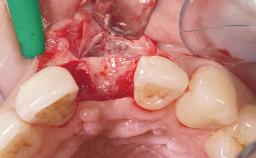

Immediate Flapless Placement of an Implant in a Maxillary Left Central Incisor Site

A 42-year-old female patient was referred to our clinic at the School of Dentistry of the University of São Paulo in November 2004, presenting a deficient restoration in the upper left central incisor. The clinical examination revealed no gingival retraction or any signs of gingival inflammation and, therefore, previous periodontal treatment was not considered. The patient presented a high lip line at full smile and a thin tissue biotype. This combination characterized a high-risk situation from an anatomic point of view, which required careful preoperative planning and cautious surgical execution.

Type of Implants One-Piece

Placement Protocol Immediate implant placement

Tooth Site Maxillary incisor or canine